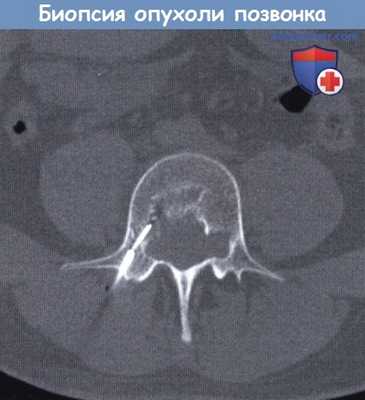

Чрескожная биопсия хордомы тела позвонка под контролем компьютерной томографии.